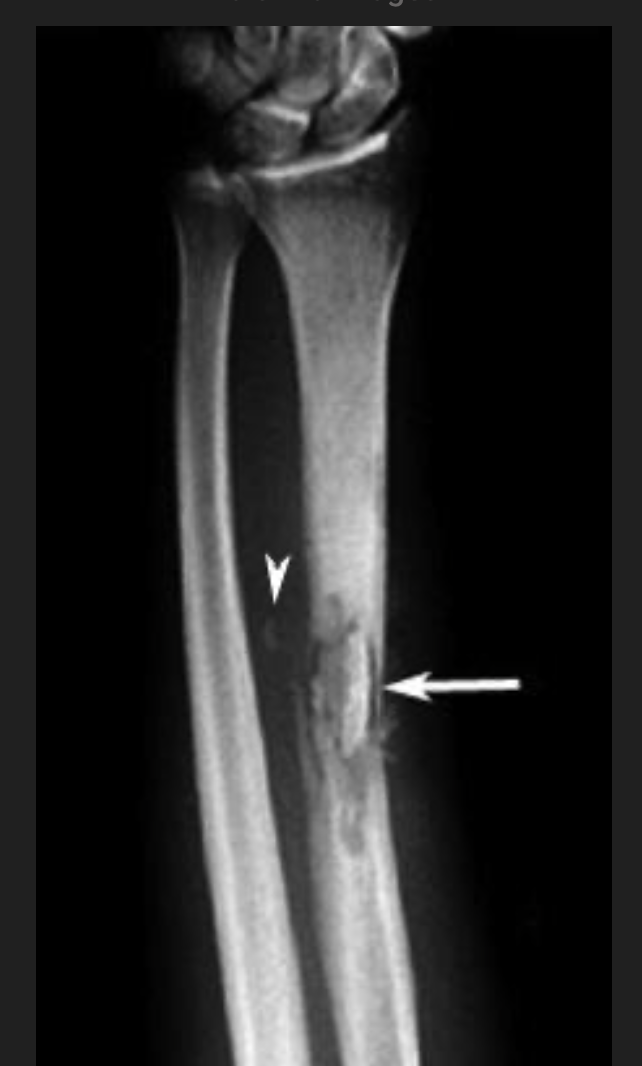

A patient presents with ?osteomyelitis. An MRI is performed.

What does the arrow point at? [1]

A

involucrum: formation of new bone around an area of bony necrosis

sequestrum: devitalized bone that serves as a nidus for infection